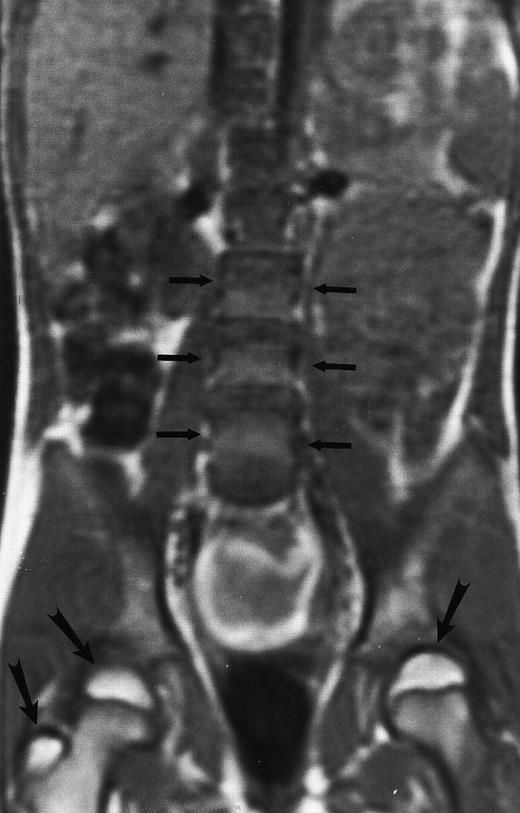

Normal bone marrow in an 8-year-old child. Coronal T1-weighted (TR/TE, 600/11) MR image of the abdomen and pelvis shows persistent red marrow in the spine (arrows). Note bright signal of fatty marrow in the femoral epiphyses and apophyses (long arrows).